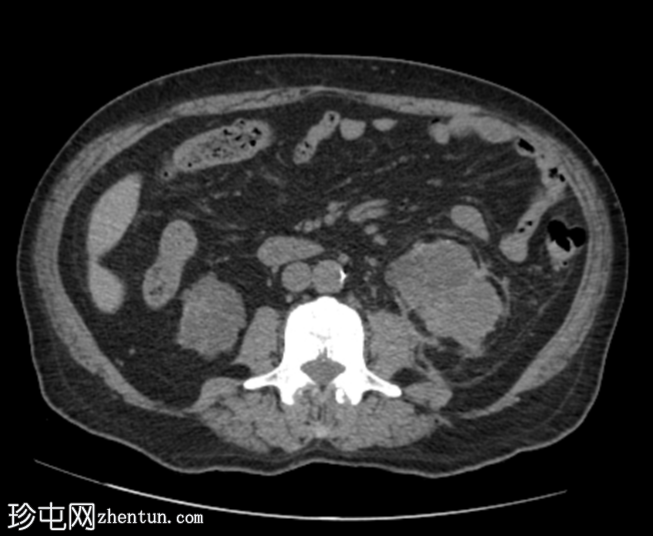

CT扫描

轴位

平扫

7.png

再次显示双侧肾囊性疾病,可见多个复杂(出血性)囊肿,以及与左肾上极复杂出血性囊肿相连的左肾周血肿。左肾周脂肪间隙模糊。

双侧多发性小肾结石。